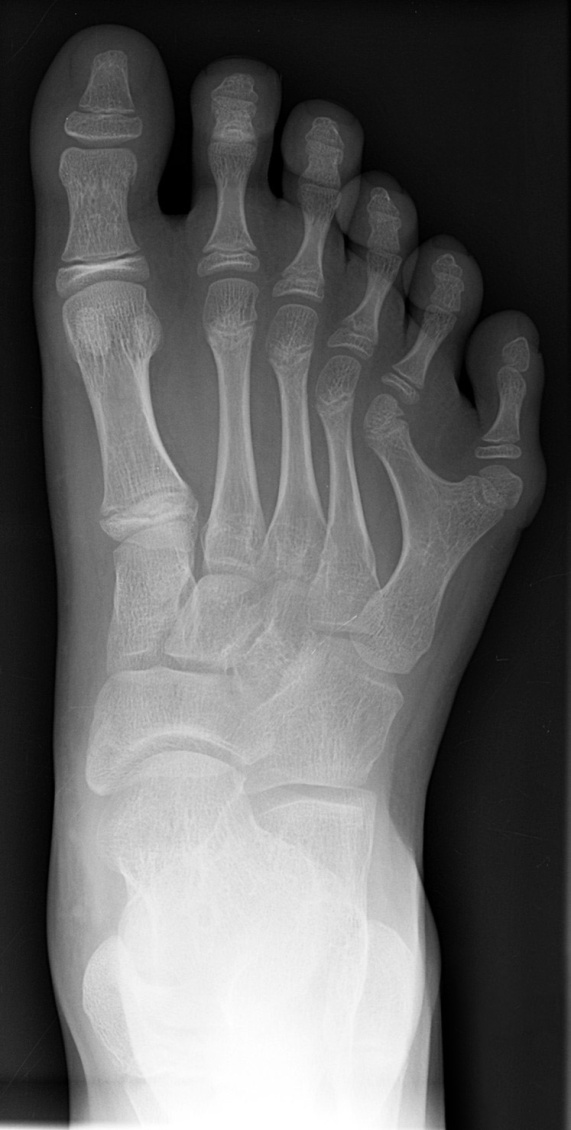

Это трисомии по 18 хромосоме (рис. 4.1). Почти во всех случаях синдром Эдвардса обусловлен простой трисомной формой (гаметическая мутация у одного из родителей). Встречаются и мозаичные формы (нерасхождение на ранних стадиях дробления). Транслокационные формы крайне редки и, как правило, это частичные, а не полные трисомии. Клинических различий между цитогенетически различающимися формами трисомии нет. Частота синдрома Эдвардса составляет 1:5000—1:7000 новорождённых. Соотношение мальчиков и девочек равно 1:3. Причины преобладания больных девочек пока неясны. При синдроме Эдвардса отмечается выраженная задержка пренатального развития при полной продолжительности беременности (роды в срок). На рис. 4.2 представлены пороки развития, характерные для синдрома Эдвардса. В первую очередь это множественные врождённые пороки развития лицевой части черепа, сердца, костной системы, половых органов. Череп долихоцефалической формы; нижняя челюсть и отверстие рта маленькие; глазные щели узкие и короткие; ушные раковины деформированные и низко расположенные. Из других внешних признаков отмечаются флексорное положение кистей, аномально развитая стопа (пятка выступает, свод провисает), I палец стоп короче II. Спинномозговая грыжа и расщелина губы встречаются редко E% случаев синдрома Эдвардса).